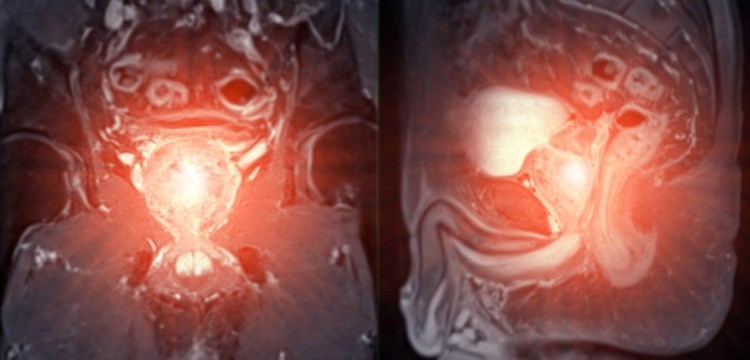

MRI של ערמונית מוגדלת. "הלחץ המתמשך על מערכת השתן עלול לגרום נזק הדרגתי לכליות". צילום: שאטרסטוק

הסיבוכים האפשריים של דחיית הטיפול יכולים להיות חמורים ומצטברים: "כאשר שלפוחית השתן אינה מתרוקנת באופן מלא, נוצרת סביבה המעודדת התפתחות זיהומים חוזרים", מסביר פרופ' סופר. "השתן העומד עלול להוביל להיווצרות אבנים בשלפוחית השתן, מצב כואב שדורש טיפול נוסף. החמור מכל הוא שהלחץ המתמשך על מערכת השתן עלול לגרום נזק הדרגתי לכליות".